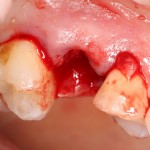

Биоматериал не нужно предварительно смачивать или увлажнять, он просто помещается в лунку в нужное положение:

Обратите внимание — у лунки отсутствует часть вестибулярной стенки. При использовании порошкообразного или гранулированного материала, мне пришлось бы отграничивать эту вестибулярную стенку с помощью барьерной мембраны. При использовании BioOss Collagen чаще всего этого не требуется.

Сам же материал достаточно гигроскопичен, чтобы быстро пропитаться кровью из лунки. Напомню, что именно жидкости являются транспортной средой в нашем организме, поэтому гидрофильные свойства во многом определяют способность биоматериала к интеграции:

Нет необходимости заполнять биоматериалом всю лунку. Не нужно заталкивать его в периапикальные области. Не забывайте о задаче — в первую очередь, нас интересует положение вестибулярной стенки, именно ее мы должны удержать на месте. Поэтому позиционируем наш графт, в основном, в верхней трети лунки: